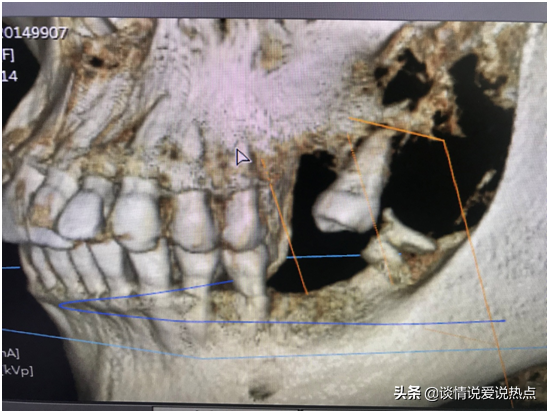

下圖是我現(xiàn)在左邊的牙齒,下頜有一顆殘根,要拔掉,上頜由于缺牙太久,旁邊那顆已經(jīng)歪得很嚴重,看到它歪成這樣我自己都被嚇到。從遠期果考慮,醫(yī)生建議拔掉再種,不然下頜種上了兩顆,與這顆的咬合關系是擁擠的,咀嚼不力,咬合關系不好,長期使用就會受影響。加上這顆牙齒有齲壞,經(jīng)過深入的考慮,我還是決定拔掉種了。